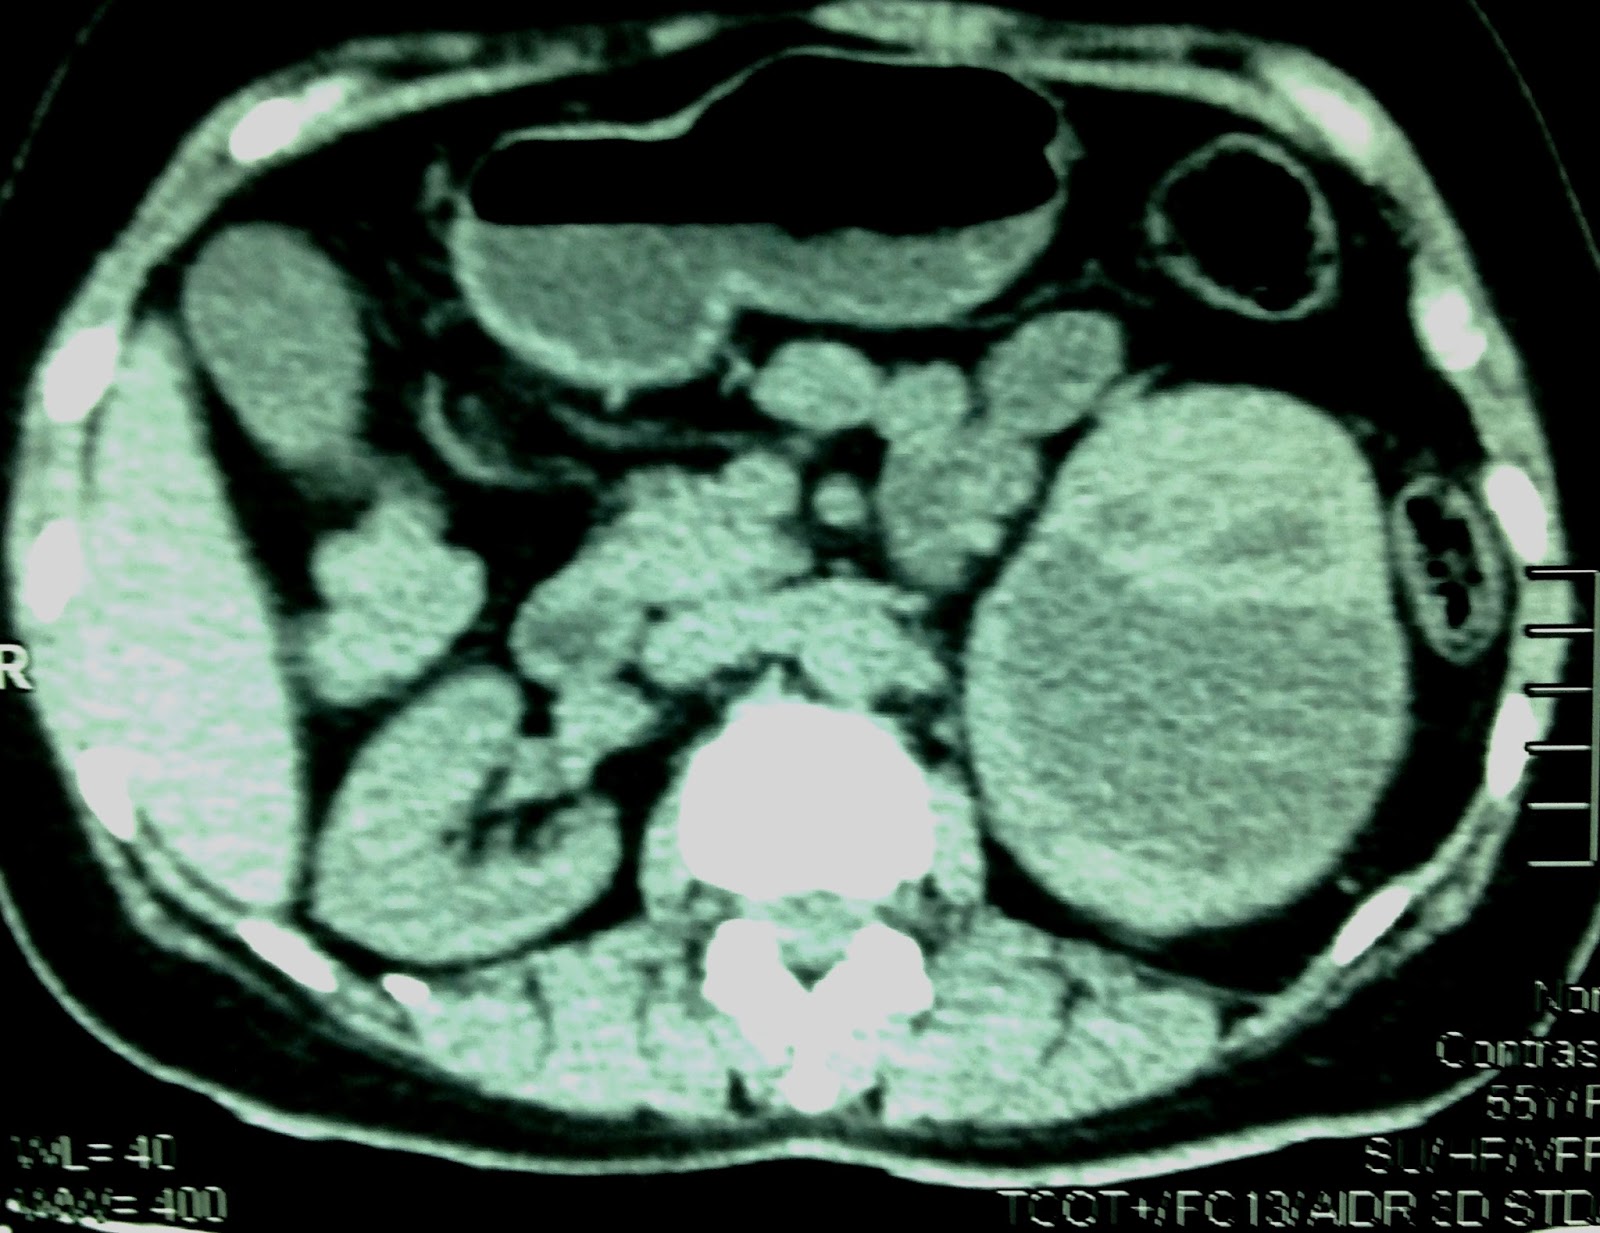

MSCT with CE= CT1: sagittal plan this mass at adrenal fossa deplaced left kidney. CT2: normal vascular supply to kidney . CT3: crossed section of.this mass inhomogeneous in contrast enhancement.